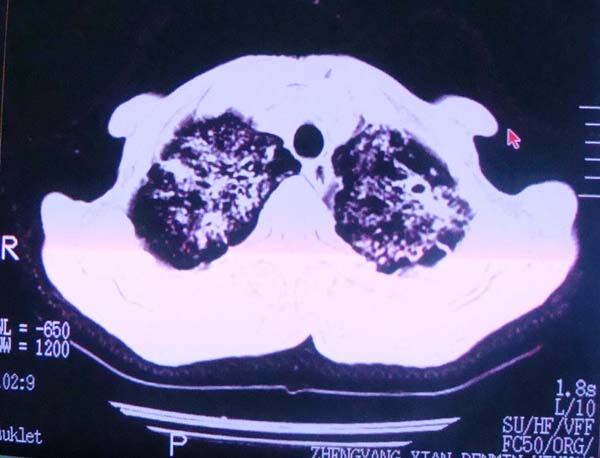

以下是引用zhangzhongshou在2008-2-15 22:25:00的发言:[br]片子照得不清,基本考虑1、细支气管肺泡癌2、亚急性血行播散型肺结核。请结合临床。片子细节显示不清,无法提供进一步意见。

以下是引用杀毒软件在2008-2-15 22:34:00的发言:[br]小叶中心性肺气肿。两肺弥漫性病变,肺泡微石病,过敏性肺炎,尘肺2期,特发性肺纤维化都有可能。[br]不象肺泡癌。